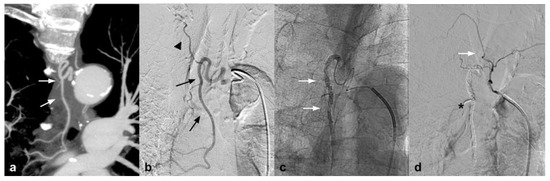

This new generation of embolizing agents has further advantages, excellent embolizing capacity of the treated vessel, and is able to reach vessels with a diameter of 80 microns (Figure 2).

Figure 2.

(a) Coronal CTA MIP demonstrates hypertrophic bronchial artery with tortuous course originating at 9:00 from the convexity of the aortic arch (white arrows); (b) DSA performed with Simmons 1 catheter at the level of the ostium of the bronchial artery confirms the presence of the hypertrophic vessel (black arrow) with a small tributary branch of the right upper lobe (arrow head); (c) single-shot fluoroscopy after embolization shows the presence of the microcatheter at the level of the proximal portion of the bronchial artery, with a Squid 12 cast completely occupying the main trunk (white arrows); (d) post-procedure DSA control demonstrates complete exclusion of the treated vessel (asterisk) with patency of the small branch for the right pulmonary upper lobe (white arrow).